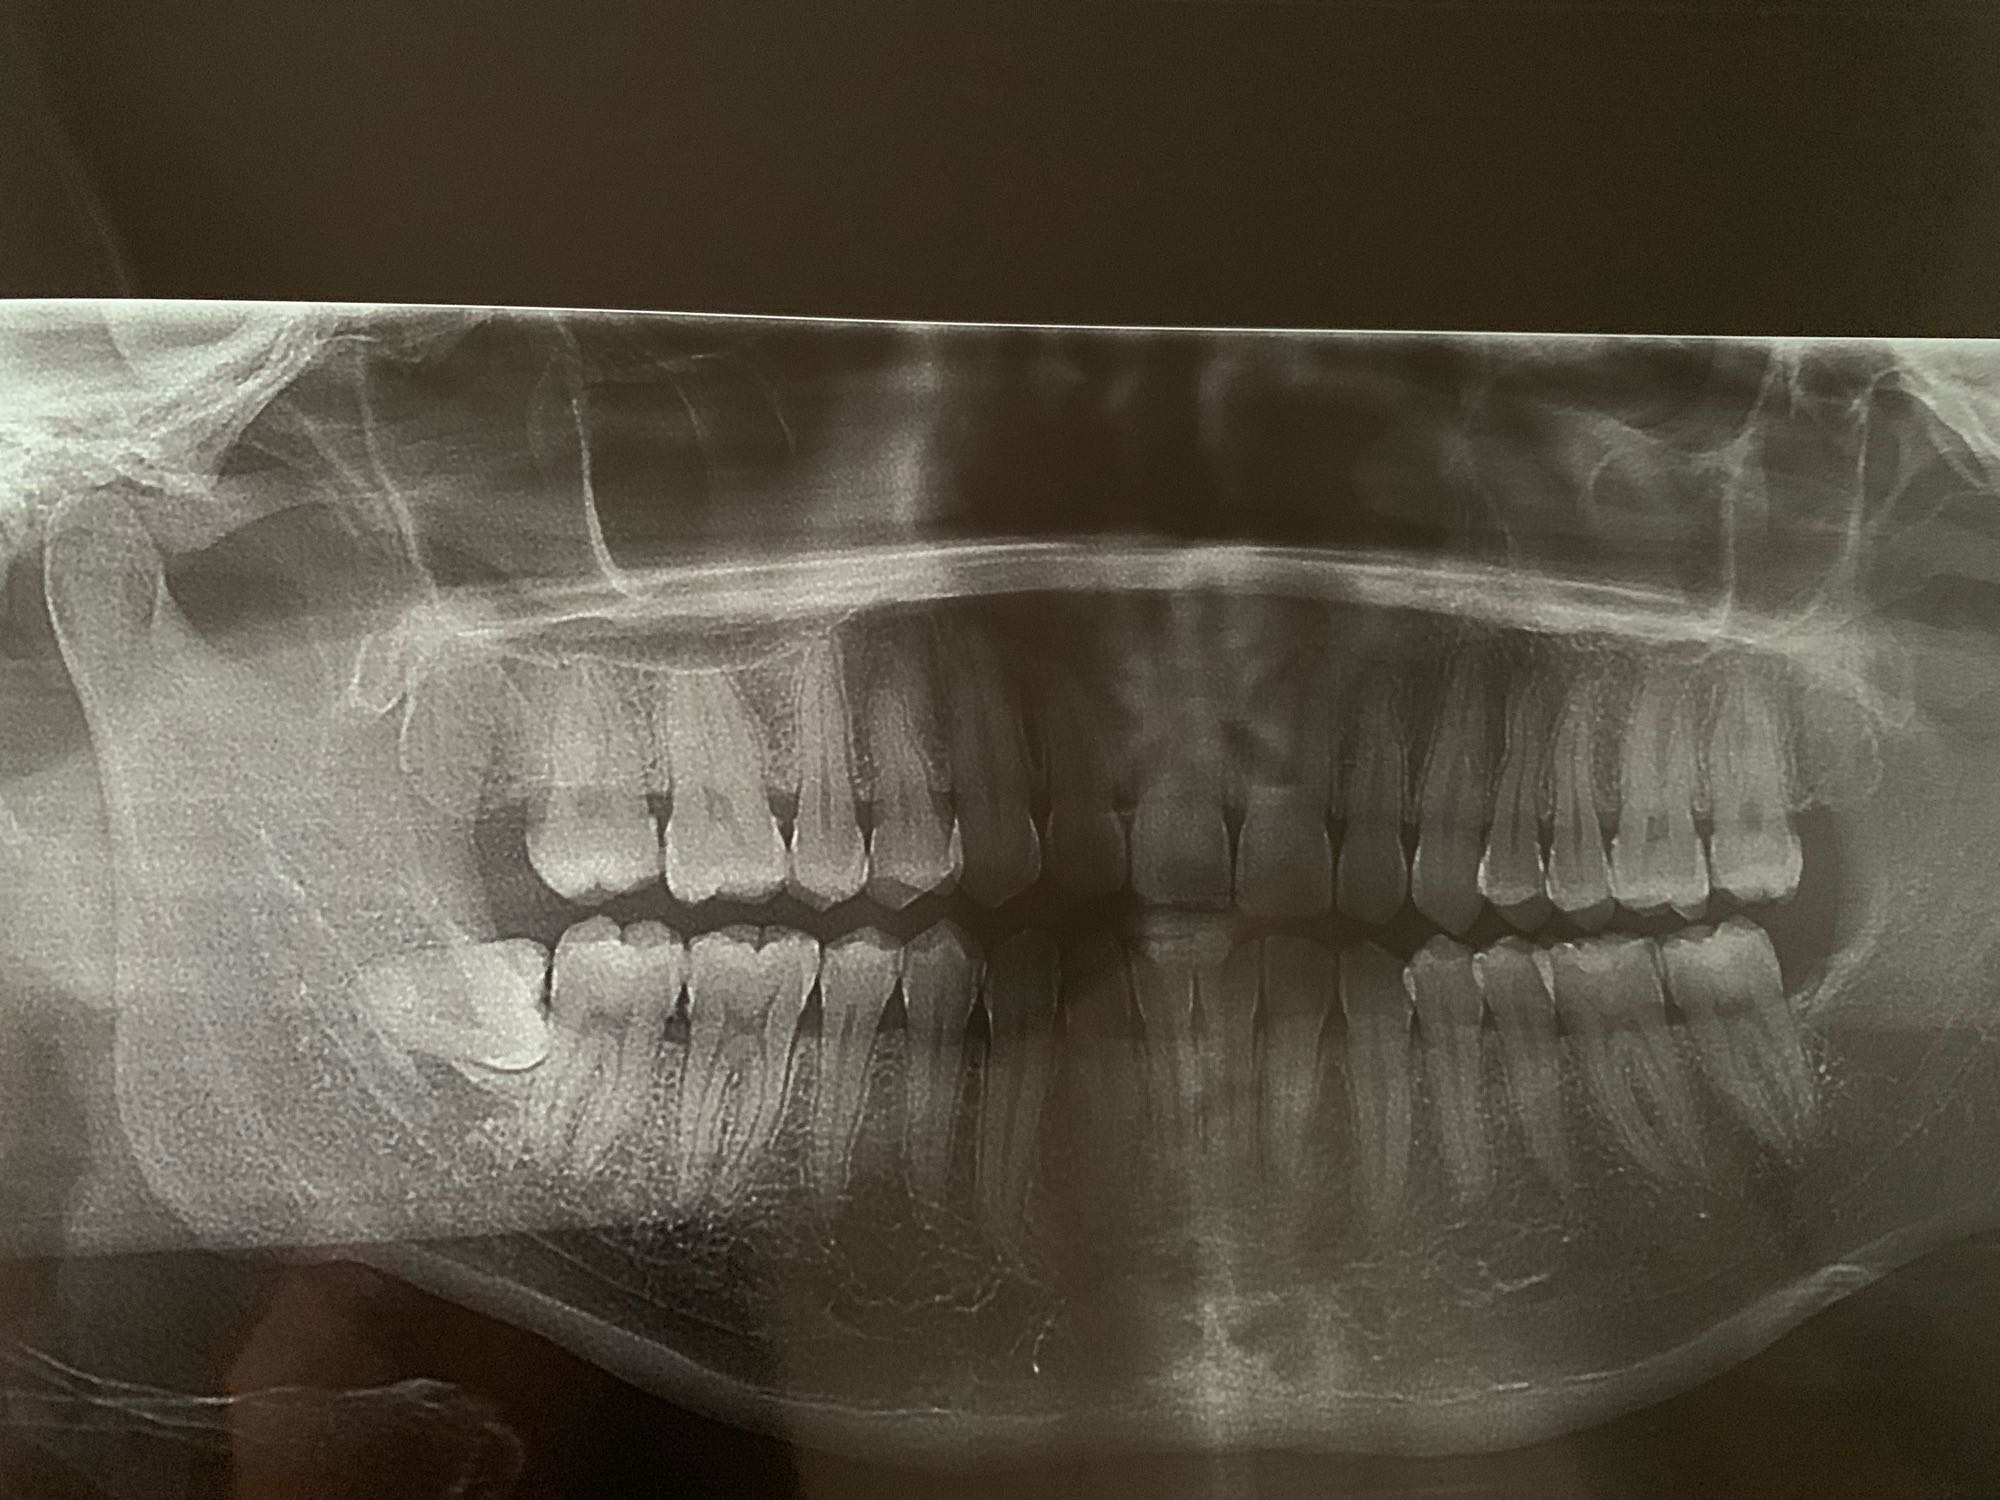

求助各位“齿友”或医生大神给看看我这个横向阻生齿拔出难度有多大?感谢。

不疼不痒不发炎,是体检时候发现长得智齿。之前已经拔过三颗了,都很顺利。这是最后一颗,昨天挂的普通医生说拔不了,要切骨,还有可能伤到神经???现在害怕的不行,求指点。

更新一下:本周二在北大口腔拔的,确实非常难拔,估计拔了至少40分钟,现在第四天,除了脸肿嘴角有一点破以外,伤口基本不疼了,因为离神经确实太近了,当天又拍了CT,目前舌头下巴嘴唇都没有出现麻木的情况,已经心满意足了。祝各位好运

这种必须拔的,我也有准备拔。这种比较麻烦要先切开牙床再切断牙齿取出牙齿最后取牙根。

如果没长出来应该是需要切骨的,这种情况最好是拔了越早越好,我的就是因为不在意,经常赛食物都已经把前面的牙蛀牙了